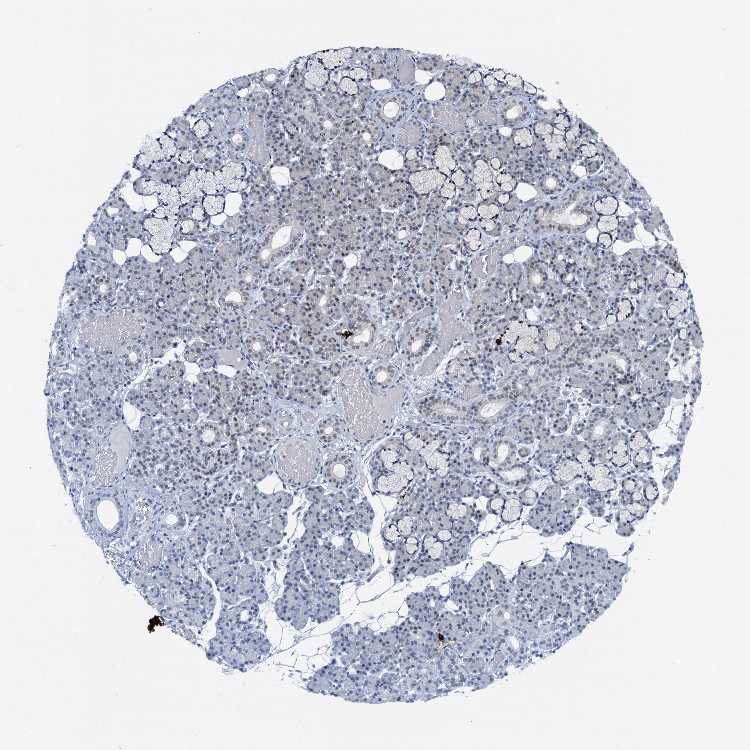

SALIVARY GLAND - Antibody stainingi

Antibody staining in the annotated cell types in the current human tissue is reported as not detected, low, medium, or high, based on conventional immunohistochemistry profiling in selected tissues. This score is based on the combination of the staining intensity and fraction of stained cells.

Each image is clickable and will lead to virtual microscopy that enables deeper exploration of all samples and also displays staining intensity scores, fraction scores and subcellular localization as well as patient and tissue information for each sample.

Antibody HPA039792

Glandular cells Low